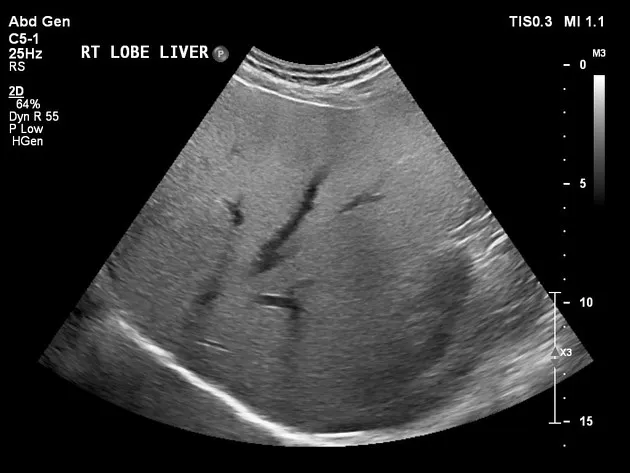

• **Elastografia Hepática** (VCTE): rigidez ≥8 kPa sugere fibrose significativa e reforça intervenção.